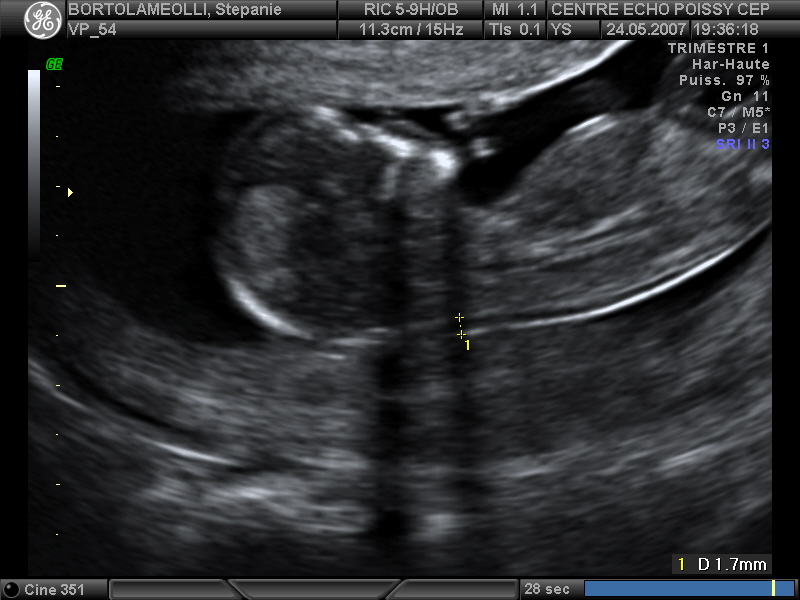

Echographies

Mai 2007